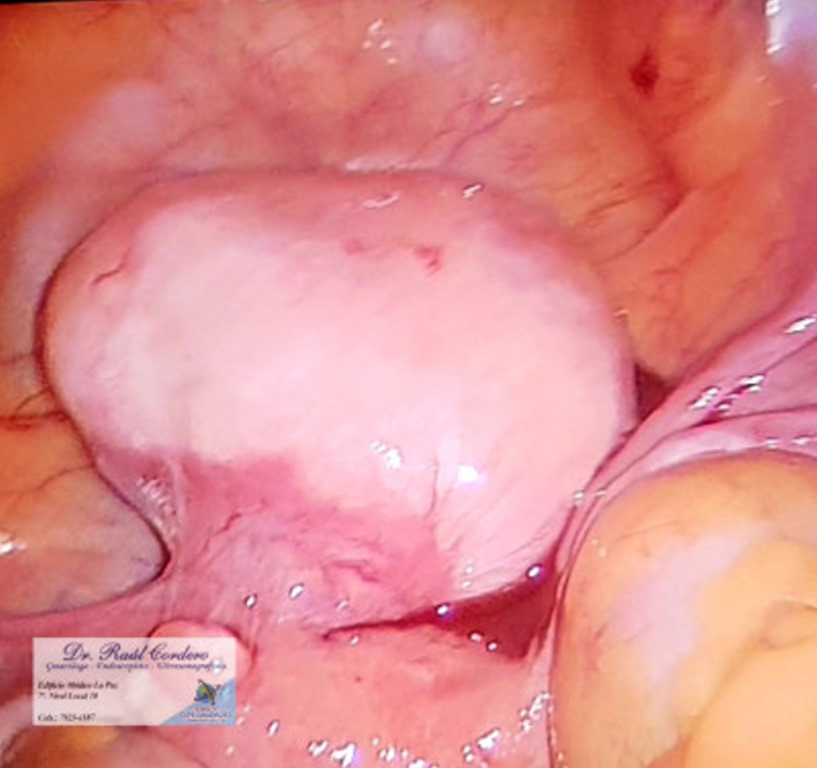

Realización de miomectomía vídeo laparoscopica